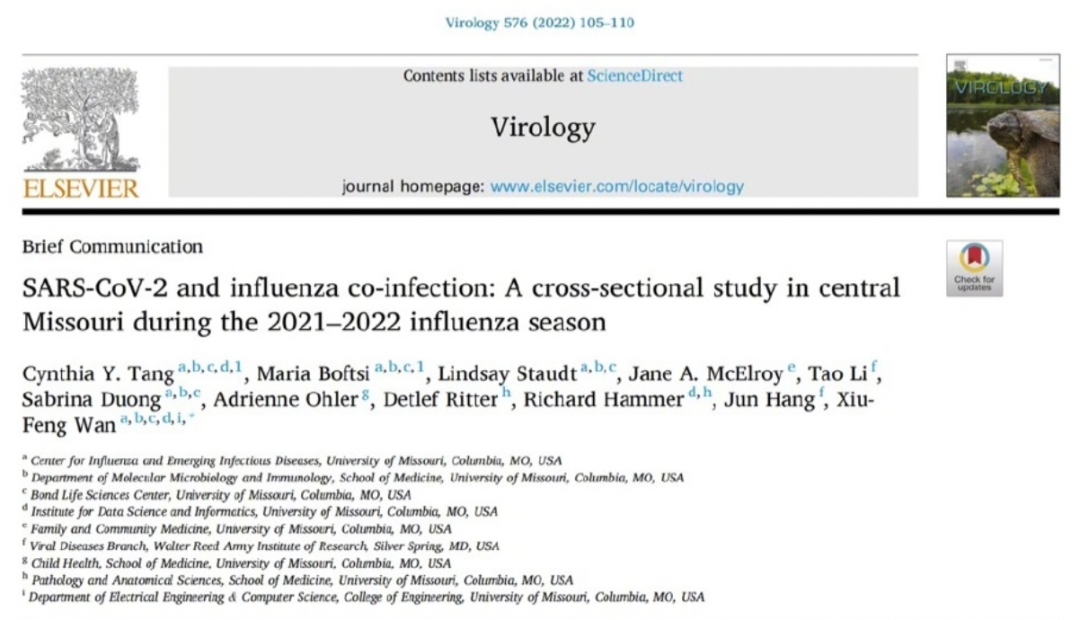

最近一项发表在《病毒学》杂志上的研究,也证实了,流感和新冠有合并感染的概率。

在2021年,美国研究机构根据密苏里州流感流行季节的统计,发现新冠病毒合并流感病毒的发生率是 33% 。

其中,新冠病毒德尔塔毒株合并流感病毒感染的概率是 44%,奥密克戎毒株合并流感病毒感染的概率是 27% 。

印度尼西亚的研究结果略有不同,甲流与新冠病毒共同感染的发生率降到了25%。